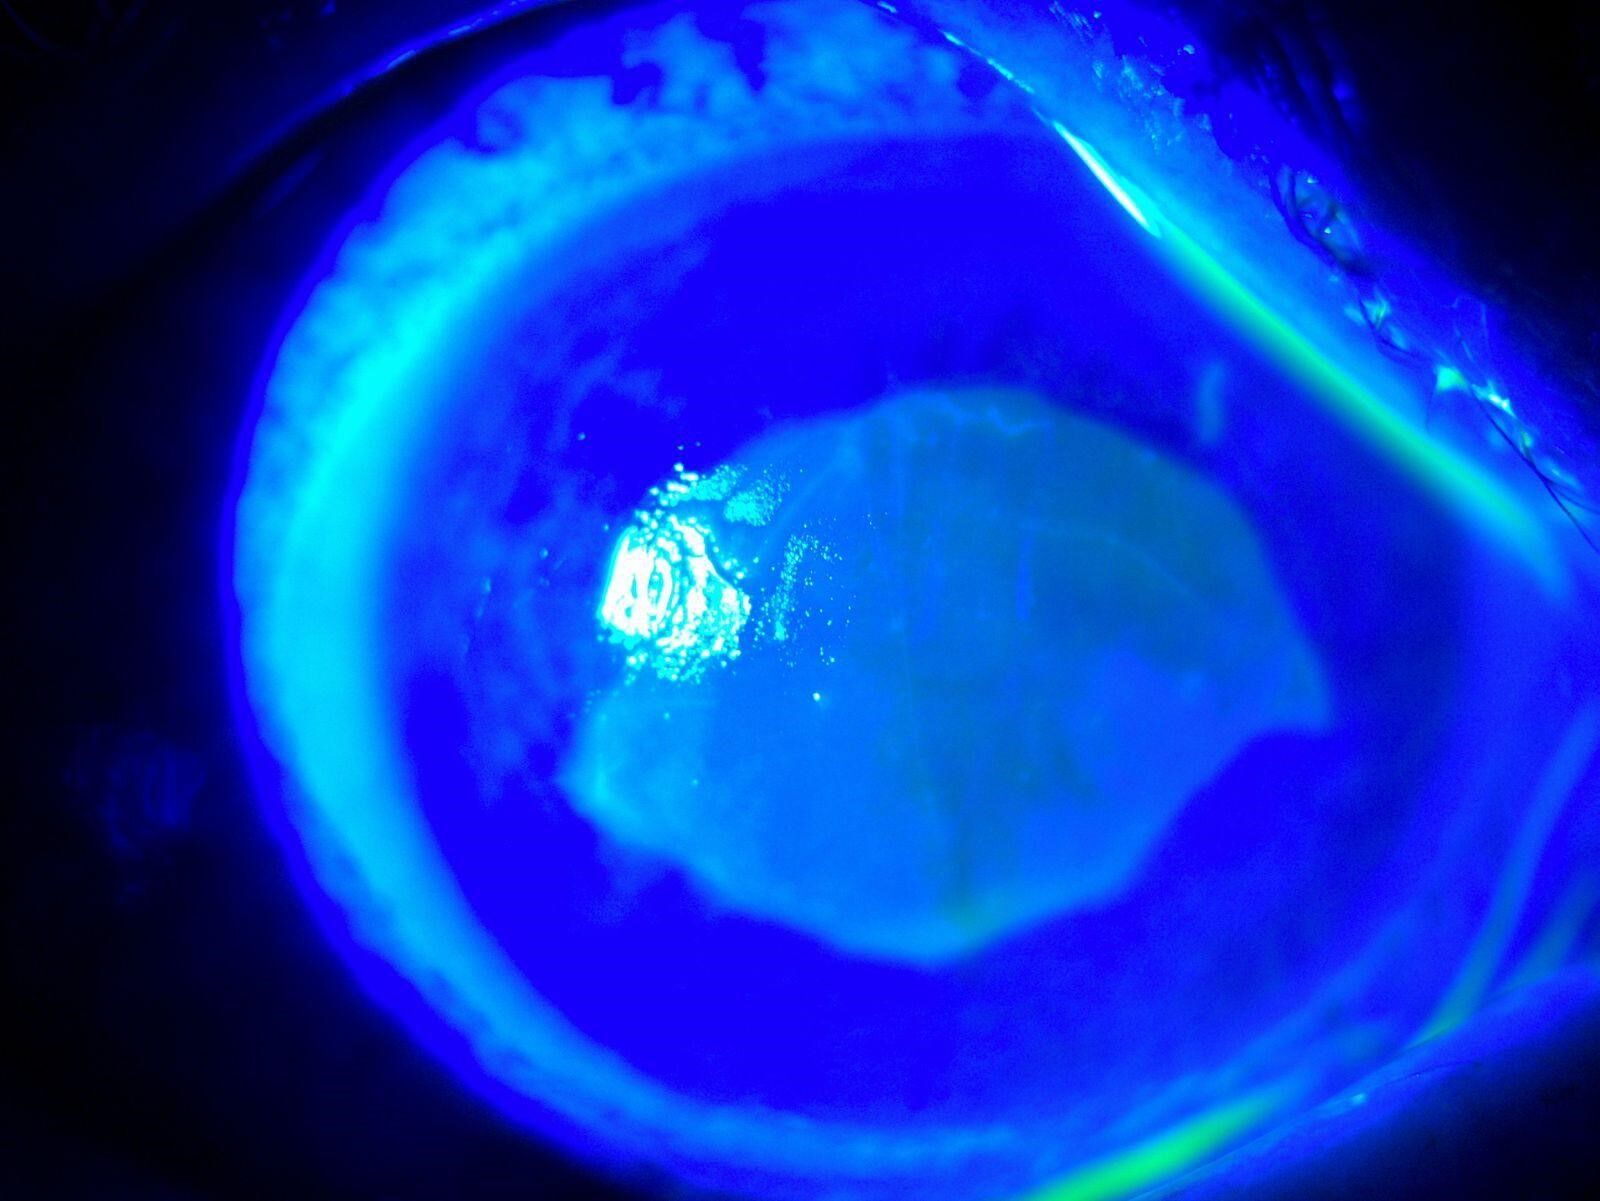

O dönem Kocaeli'nde çalışan Göz Hastalıkları Uzmanı Doç. Dr. Ömer Faruk Yılmaz ve ekibi hastaya müdahale ederken korneanın en dış katmanı olarak ifade edilen kornea epitelinin zarar gördüğü belirlendi. Göze yabancı cisim, kimyasal madde kaçması ya da enfeksiyon durumlarında gözü temizlemek amacıyla uygulanan göz yıkama tedavisi gerçekleştirildi. Yaklaşık 2 haftalık tedavinin ardından hasta sağlığına kavuştu. Doç. Dr. Yılmaz, hastasının yaşadığı süreç ve tedavisine ilişkin bilgi verdi. Yılmaz, hekim önerisi olmadan herhangi bir ürün kullanılmaması gerektiğine dikkat çekerek önemli uyarılarda bulundu. Öte yandan hastanın göz bebeğinin beyazlığı ve göz akının ise kızardığı hali fotoğraf karesine yansıdı.

"Kırlangıç otu kullandı, hastamız göremez hale geldi eğer tedavi edilmeseydi sonucun ne olacağını bilemiyoruz fakat tedavi sonucunda hastamız iyileşti. Gözlerinin fotoğrafını çektirdim, kırlangıç otunun geçişini gösterdik. Tedavi edilmediği zaman göz içinde belki de körlüğe ulaşabilecek şekilde istenmeyen yan etkilere yol açabilir. Yüzlerce farklı ot olabilir, yanlışlıkla faydalı bir ot damlatacağız diye zararlı bir otu damlatabiliriz. Göze direkt damlatılması steril değildir, göze zarar verebilir, enfeksiyon oluşturabilir. Faydalı bile olsa Sağlık Bakanlığı ruhsat vermeden, ilaç formatına dönüştürmeden, uygun dozajlar ayarlanmadan ve göz hekiminin önerisi olmadan göze herhangi bir bitkisel ilaç damlatılmasını önermiyoruz."